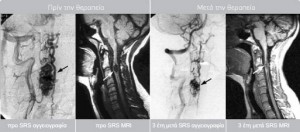

Η επιτυχία που παρατηρείται στην ακτινοχειρουργική αντιμετώπιση των αγγειακών δυσπλασιών του εγκεφάλου προβλέπεται να επαναληφθεί στην σπονδυλική στήλη και άλλα σημεία του σώματος.

Το κέντρο μας διαθέτει μεγάλη εμπειρία στην αντιμετώπιση αγγειακών δυσπλασιών και σηραγγωδών αιμαγγειωμάτων.

Έχουμε αντιμετώπιση περισσότερο από 131 ασθενείς με AVM, με ποσοστό εξάλειψης >90% στη διετία. Αναμένεται από τη θεραπεία μείωση του όγκου του AVM κατά 50% με το μέγιστο να καταγράφεται στην τριετία όποτε και αν υπάρχει υπολειπόμενος ιστός και εφόσον κριθεί απαραίτητο να χορηγείται με ασφάλεια συμπληρωματική δόση.